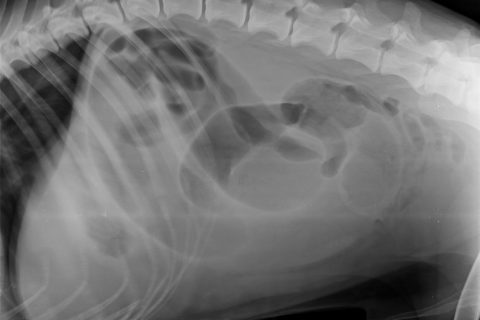

Lažan i fasificiran nalaz mišljenje veterinarske ambulante Lonjica koji dokazuje moje tvrdnje o prikrivanju istine što je detaljno pojašnjeno u video zapisu.

Niti 13.4. niti 14.4. nije rađena ultrazvučna pretraga koja je ovdje napisana za 13. travanj 2021. Nije uočena nikakva tvorba u području mezogastrija. Rtg koji je rađen dva dana, nije ovdje niti spomenut. Nisam odbio patohistološku pretragu i razudbu jer mi ista nije niti ponuđena. To su trebali sami napraviti, ali nisu jer bi se otkrila istina.